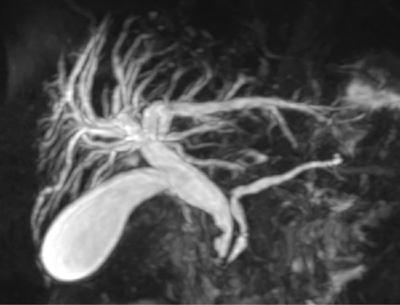

Shrinivas B. Desai, Ritu K. Kashikar, Shreya Shukla Radiological signs are classical and distinctive abnormalities characteristic of a disease. These can be seen on any imaging modality. Resemblance to commonly seen objects and patterns form the basis of radiological signs. The aim is to help the reader associate, understand and memorize these pathologies with the aid of signs. Various signs pertinent to hepatobiliary system are described in the chapter. Described on MRI when liver lesion shows a peripheral rim of high T2 signal intensity with the centre of the lesion appearing isointense to the background of noncirrhotic liver on T2WI mimicking an atoll. It is considered a characteristic sign of an inflammatory hepatic adenoma (image) but is only seen in about one-third of cases Extrinsic smooth impression over medial aspect of duodenum along its posteroinferior aspect, seen in pancreatic head pathologies like carcinoma. This sign is seen in pancreatic adenocarcinoma Presence of a persistently hyperattenuating dot within a lesion on arterial and portal venous CT. This corresponds with peripheral nodular enhancement seen on dynamic MR. Presence of bright dot suggests that the lesion is a hemangioma and helps in ruling out metastasis Ultrasound appearance of multiple cystic spaces or lesions that has been used to describe the appearance of an intraductal papillary mucinous neoplasm of the pancreas. Seen on contrast CT in portal hypertension. The appearance is based on resemblance to Medusa from Greek mythology. Dilated engorged paraumbilical veins radiating across umbilicus to join systemic veins is seen. This sign is seen in Caroli’s disease on contrast CT. Enhancing dots within dilated intrahepatic bile ducts represent portal radicles. Caroli’s disease Irregularly dilated pancreatic duct with multiple strictures and intervening dilatation with associated dilated side ductules resemble multiple lakes supplied by a single territory. Best seen in MRCP images. Chronic pancreatitis It is a finding on MRI and CT and is best seen on MRI T2-weighted and postcontrast T1-weighted sequences. Small necrotic/purulent areas in the pyogenic abscess ‘cluster’ together and then coalesce into a larger necrotic/purulent areas, eventually becoming a larger septated abscess cavity. At the periphery of these clusters: Associated with pyogenic hepatic abscesses and can help differentiate pyogenic abscesses from other types of liver lesions Abrupt termination of gas within the proximal colon at the level of radiological splenic flexure. The inflammatory exudates in pancreatitis extend to the phrenicocolic ligament giving rise to this sign Seen on grey scale ultrasound as a reverberation artifact when small calcific or highly reflective objects are imaged. The colour comet-tail artifact is an ultrasonographic sign seen in a number of situations when colour Doppler scanning is performed. This sign occurs in cases of traumatic right-sided diaphragmatic rupture with resultant partial herniation of liver through the defect. Separation of the herniated liver from its intra-abdominal component is via a small constriction at the level of diaphragm resembling a cottage loaf. Cottage loaf is a particular shape of bread in which larger and smaller roughly spherical balls are squashed together. Traumatic right-sided diaphragmatic rupture with resultant partial herniation of liver Bile eccentrically outlines luminal stone, creating a low attenuation crescent. Best seen on MRCP images. Choledocholithiasis Dilatation of both pancreatic duct and CBD is referred to as the double duct sign. Positive double duct sign suggests the diagnosis of carcinoma of the head of the pancreas and ampullary tumours and is hence considered ominous. Occasionally the sign may be seen in impacted gallstone in the distal duct. This feature is seen in patients with liver abscess on contrast-enhanced CT. A double, inner hyperattenuating and outer hypoattenuating rim is seen surrounding the hypodense abscess. The inner hyperattenuating rim corresponds to the enhancing abscess membrane, while the outer rim corresponds to the edema of the surrounding liver which appears hypodense and may show delayed enhancement. Liver abscess A positive duct penetrating sign is when a mass is penetrated by an unobstructed pancreatic duct; this makes focal pancreatitis the most likely cause rather than pancreatic carcinoma. This sign is best appreciated on MRCP (or ERCP). A radiographic sign that can be useful in differentiating between focal pancreatitis (inflammatory pancreatic mass) from pancreatic carcinoma. The duct-penetrating sign on MRCP is more helpful in differentiating between these two entities than a delayed enhancement pattern on CT or MRI It occurs when there is both limy bile and a gallstone in the common bile duct. The linear vertical radiopaque bile forms the line of the exclamation mark (i.e. !), whilst a more distal calculus forms the ‘dot’ at the end of the exclamation mark. Pathognomonic imaging sign of the rare diagnosis of limy bile on plain abdominal radiography Nonenhancing ruptured lesion with peripheral rim enhancement showing discontinuity from the rest of the liver and protruding from the liver surface is called the enucleation sign. Ruptured HCC Enlargement of the pericholecystic space. One of the signs of liver cirrhosis Can be seen on technetium 99m sulphur colloid scans of the liver and spleen, as well as CT studies. It occurs as a focal area of increased radiopharmaceutical uptake in the medial segment of the left hepatic lobe (segment IV) occurring as a result of SVC obstruction and portosystemic venous shunting between the superior vena cava and the left portal vein via the internal thoracic and paraumbilical veins. The equivalent of this sign may also be seen on contrast-enhanced CT scans as a hypervascular region. Budd–Chiari syndrome causes the hot spot sign in the caudate lobe

17) Duct penetrating sign